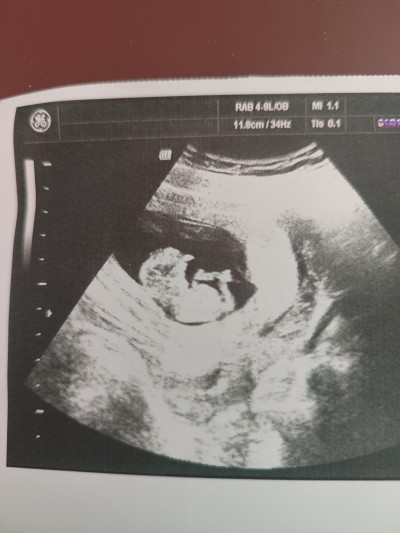

14+1 haftalık hamileyim bebeğim hareketli olduğunu söyledi ama hala bı cinsiyet belirtmesi doktorum .Cinsiyet tahmini olan var mı merak ediyorum cinsiyeti.

Kız gibi geldi